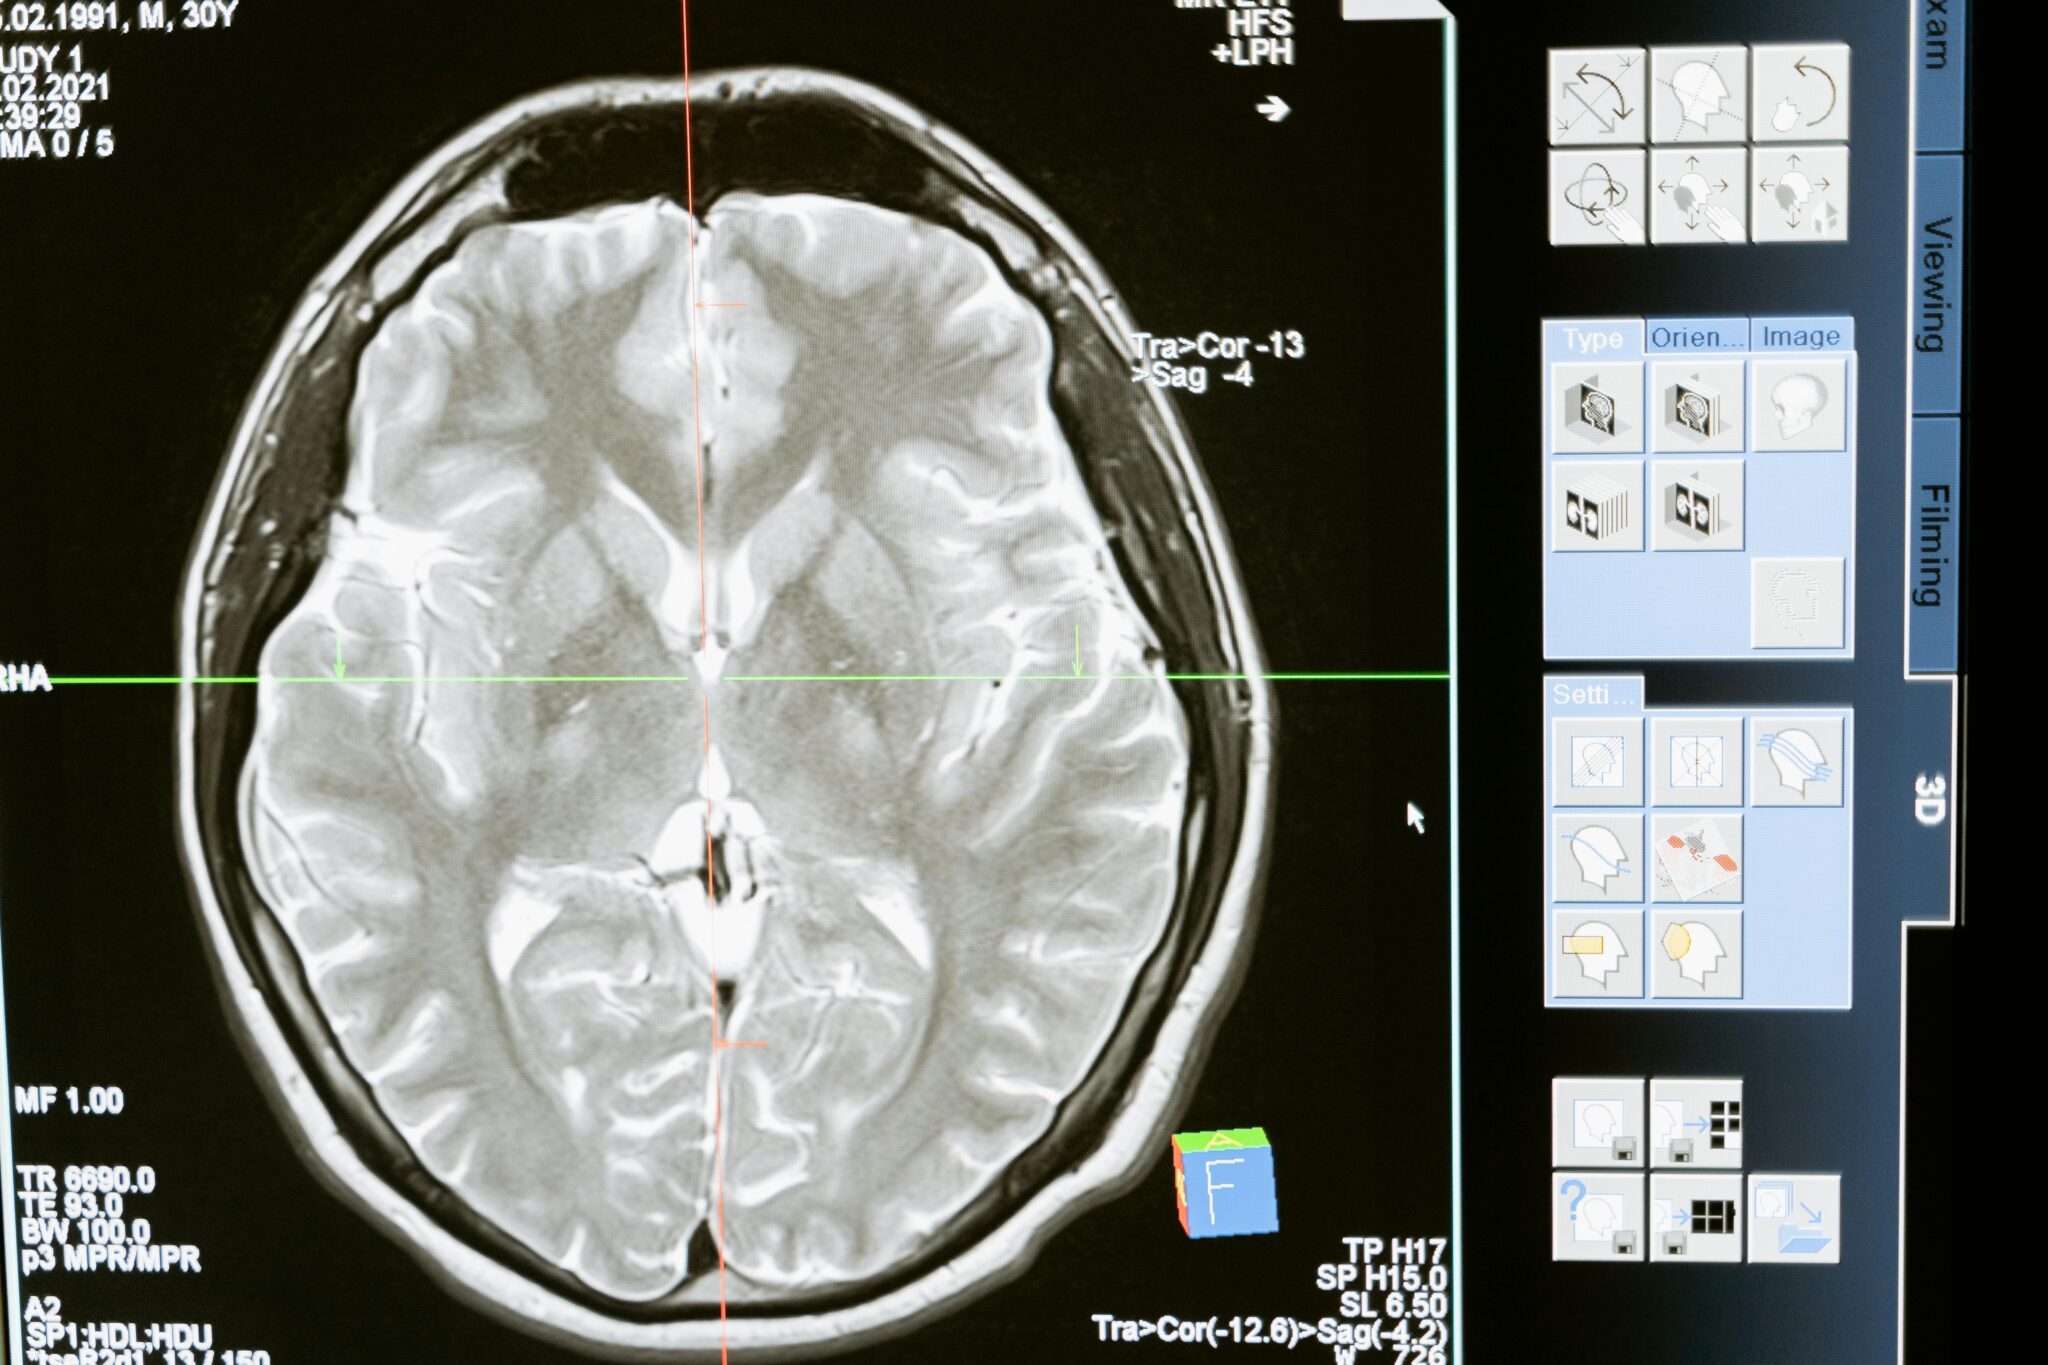

Kanadyjscy naukowcy sprawdzili, jak ChatGPT radzi sobie w diagnostyce medycznej. Sprawdzali prawidłowość stawianych diagnoz oraz sposób komunikacji. Doszli do wniosku, że chociaż potrafi on pisać czytelne odpowiedzi, to w połowie przypadków podaje błędne diagnozy. ChatGPT nie daje zgodnych z faktami diagnoz „mimo obszernej informacji, na której był trenowany, a poprawne odpowiedzi dawał tylko w 49 … Czytaj dalej ChatGPT bardzo słabo radzi sobie w medycynie